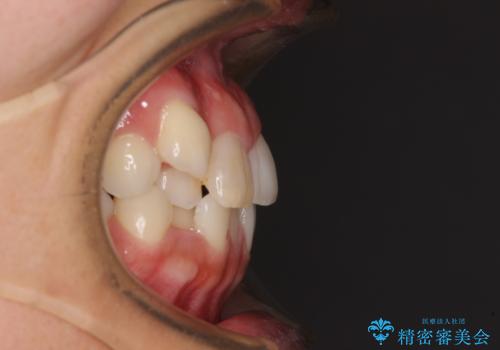

気になる八重歯 目立ちにくいハーフリンガルでの抜歯矯正

- 八重歯や前歯のデコボコを気にして来院された患者様です。

目立たない装置を希望されたので、上顎が裏側装置のハーフリンガルを選択し、上下左右の小臼歯(計4歯)を抜歯して矯正治療を行うこととしました。